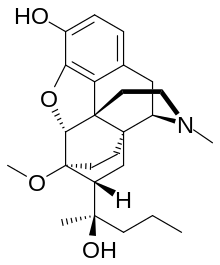

Several semi-synthetic opioids were developed in Germany in the 1910s. The first, oxymorphone, was synthesized from thebaine, an opioid alkaloid in opium poppies, in 1914.[228] Next, Martin Freund and Edmund Speyer developed oxycodone, also from thebaine, at the University of Frankfurt in 1916.[229] In 1920, hydrocodone was prepared by Carl Mannich and Helene Löwenheim, deriving it from codeine. In 1924, hydromorphone was synthesized by adding hydrogen to morphine. Etorphine was synthesized in 1960, from the oripavine in opium poppy straw. Buprenorphine was discovered in 1972.[228]

The first fully synthetic opioid was meperidine (later demerol), found serendipitously by German chemist Otto Eisleb (or Eislib) at IG Farben in 1932.[228] Meperidine was the first opiate to have a structure unrelated to morphine, but with opiate-like properties.[199] Its analgesic effects were discovered by Otto Schaumann in 1939.[228] Gustav Ehrhart and Max Bockmühl, also at IG Farben, built on the work of Eisleb and Schaumann. They developed "Hoechst 10820" (later methadone) around 1937.[230] In 1959 the Belgian physician Paul Janssen developed fentanyl, a synthetic drug with 30 to 50 times the potency of heroin.[211][231] Nearly 150 synthetic opioids are now known.[228]